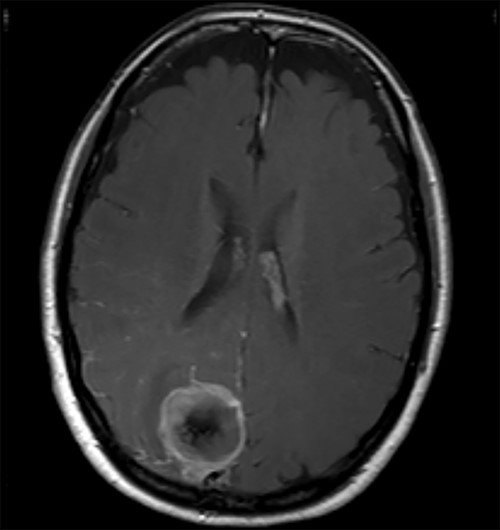

The operation was successful with a post-operative MRI within 48 h demonstrating complete resection of the tumour and resolution of the cystic lesions, but persisting intraparenchymal oedema (Fig. 3). The patient had an uncomplicated two-day stay in a neurosurgery high dependency unit postoperatively before being stepped down to the general neurosurgery ward. She was reviewed by the microbiology team and worked up for the source of infection. Blood cultures, urine cultures, CXR and transthoracic echocardiography were all negative for a source of infection. Intra-operative pus cultures isolated MSSA. The histopathology of the tumour was Meningioma WHO Grade 1 with large areas of necrosis and secondary abscess formation. She was discharged feeling well 5 days later after a satisfactory biochemical and clinical response. She was given a weaning course of steroids and a 6-week course of intravenous ceftriaxone via a PICC line as an outpatient as per microbiology advice. Ophthalmology assessment 3 months after discharge confirmed a left inferior quadrantonopia and preserved visual acuity. Repeat MRI and clinic review 8 weeks later showed no radiological residual tumour or oedema (Fig. 4), and the patient’s limb function recovered completely but had ongoing visual symptoms.

T1 weighted axial MRI post-gadolinium enhancement 8 weeks postdischarge. Right occipital postsurgical appearances are again demonstrated with reduction in the extent of vasogenic oedema. The enhancing rim that was present previously has retracted, with only focal curvilinear enhancement now evident in the right occipital lobe. These appearances are likely postsurgical/treatment related, and there is no convincing residual or recurrent disease.